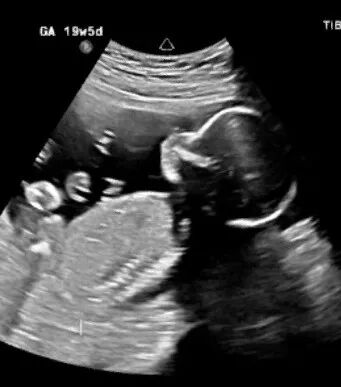

PART.03跨境管理别忽视,这三个 “避坑点” 要记牢成功妊娠不是终点,跨境孕期管理的衔接更考验功夫。生殖中心为爱心麻麻建立专属档案,每次产检报告由吉国医生同步解读;夫妇俩每周与爱心麻麻视频沟通,海外同事协调翻译与生活照料,形成 “三方联动”。如今爱心麻麻已进入孕中期,各项指标正常。回顾这段路,李先生夫妇最想分享的是:跨境试管的成功,从来不是 “赌运气”,而是选对合规目的地、吃透科学流程、守住避坑底线。